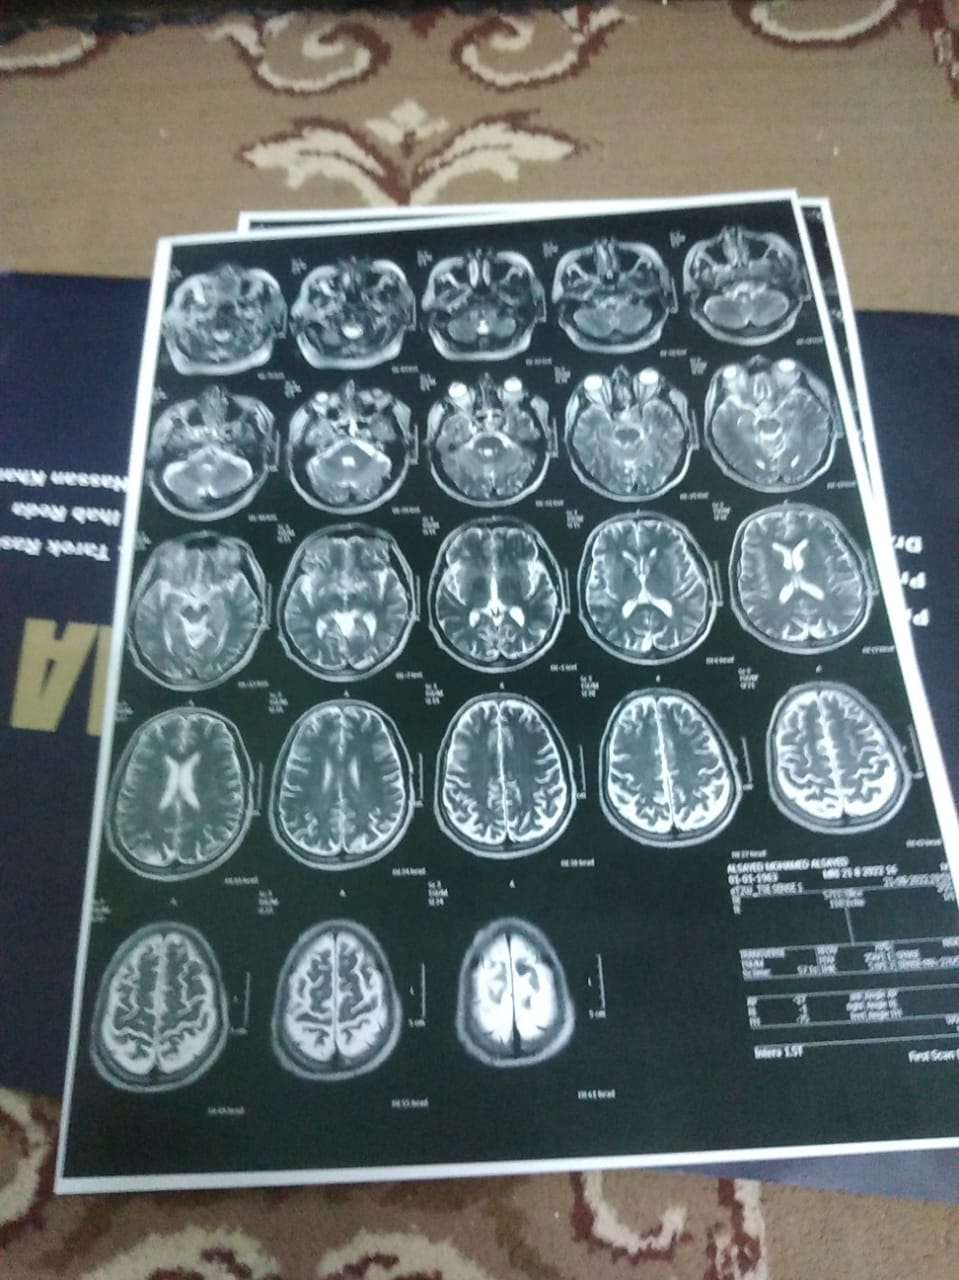

أنا مواطن مصري وموظف بشركة مصر للغزل والنسيج بكفر الدوار، أعاني من ورم بالمخ منذ يوم 16-8.. لافتة حملها مواطن مصري يدعى السيد محمد السيد موسى، صاحب الـ 49 عاما بإحدى الشوارع، يستغيث خلالها بالمسئولين لعلاجه من مرضه الذي لا يقدر عليه.

وأشارت إلى أن المرض أثر على صحته، حيث تسبب في أنه عينه الشمال أغلقت، فقالت: عينه الشمال اتقفلت، والمرض أثر على العصب الثالث والرابع والسادس، ودلوقتي أثر على عينه اليمين، ومش بيقدر يقوم يعمل أي حاجة من غيري.